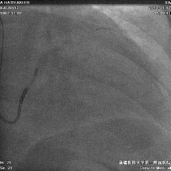

冠状静脉造影

● 通过长鞘造影,先冒烟,确认无夹层,造影后发现侧静脉分支,但不清楚远端情况。

鞘中鞘超选靶血管

● 使用鞘中鞘超选入靶血管

鞘中鞘造影

● 由于入口处有夹角,鞘中鞘无法深入,无论换用90还是130的鞘中鞘,开口处造影都看不到远端血管情况。